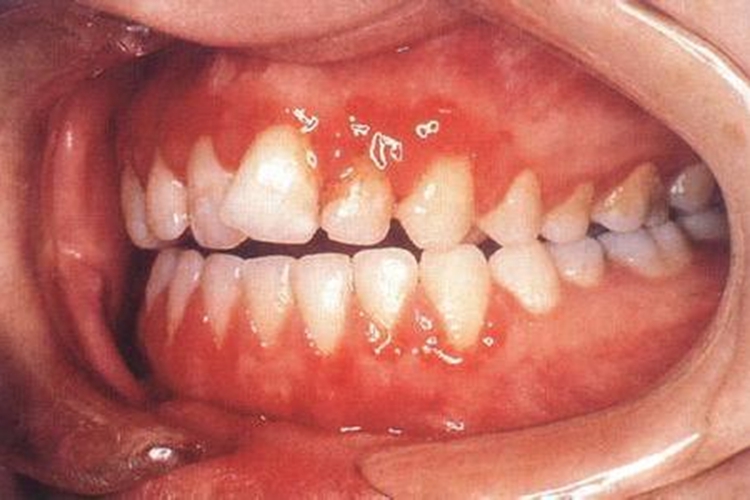

急性坏死性溃疡性龈炎:以龈乳头和龈缘的坏死为其特征性损害,尤以下前牙多见,个别龈乳头顶端可发生坏死性溃疡,上覆有灰白色坏死物,中央凹下如火山口状。龈缘如虫蚀状,坏死区出现灰褐色假膜,擦去后可见出血创面。病损一般不波及附着龈。患处牙龈极易出血,甚至有自发性出血。患者疼痛明显并有典型的腐败性口臭。